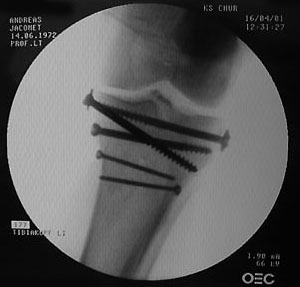

Belastet werden darf die ganze Konstruktion allerdings nicht, zumindest sechs Wochen lang - Titan und Edelstahl zierten für die nächsten Monate das Schienbein; ans Tageslicht kamen die erstaunlich grossen Schrauben erst im November wieder. Die folgenden Bilder wurden während der Operation gemacht: